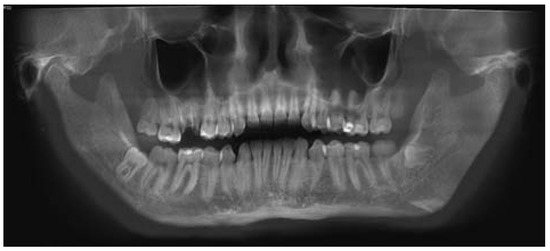

The extra- and intraoral evaluation revealed a bilateral masseter muscle hypertrophy and a buccal fat pad overgrowth in a square-face type, an increase of the mandibular angle, a class I molar occlusion with a limitation of mouth opening; we noticed even bruxism as an interpretation of his grinded teeth. The methods used for the measurement of the buccal fat pad and masseter muscle were just clinical judgment. There was no history of trauma in this patient and no genetic alteration. The orthopantomography, the computed tomographic scan, and the ultrasound did not reveal any other underlying pathology (Figure 2).

Figure 2. Preoperative mandibular Rx.